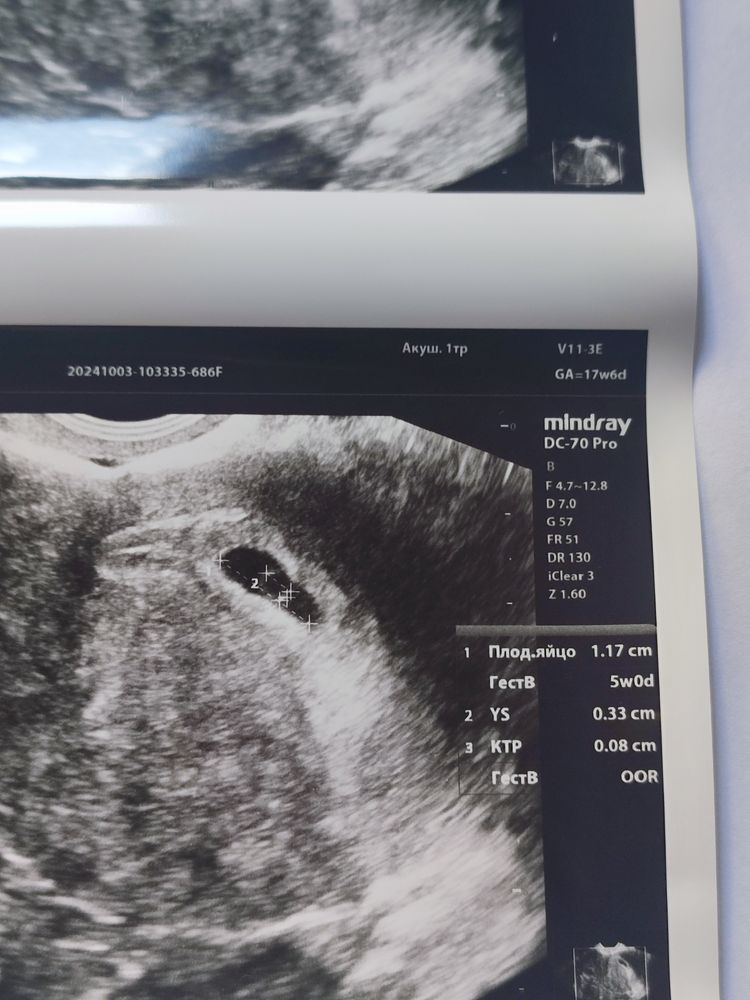

Жанна, у меня уже 4😂😂а срок всего 6 недель, хотя врач почему-то 5.2 по переносу ставит (я так и не поняла, почему)

УЗИ- контроль через 2,5 недели после чистки: Идем на крио! Второй Скрининг,20 недель,и 280 грамм счастья🥰